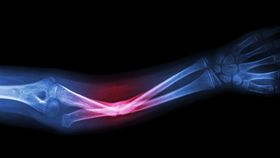

Breaks or defects in bones can be tricky and painful to treat, as surgeons often take bone from one region and use that to patch up the fracture. But now researchers have developed a new 3D-printed implant that not only removes this process, but which the body will eventually turn into real bone.

The rest of this article is behind a paywall. Please sign in or subscribe to access the full content.The implants are printed using an ink that is comprised of hydroxyapatite – a calcium mineral that's naturally found in bone – and the natural polymer PLGA. The polymer not only holds the hydroxyapatite together, but also gives the scaffold an incredible degree of flexibility, something the researchers were not expecting. The entire thing can be crushed and yet still spring back to its original shape. This means that during an operation, if the implant is the wrong shape or size, surgeons could alter and manipulate it in the operating room.

The microscopic structure of the implant is designed to mimic that of real bone, which allows the body’s own cells and blood vessels to naturally populate the scaffold. Because the implant is made from hydroxyapatite, it provides the perfect environment for bone regeneration, inducing the cells to begin the process of mineralization. Eventually, the artificial implant will become real bone.

“Cells can sense the hydroxyapatite and respond to its bioactivity,” explains Ramille N. Shah, who led the research published in Science Translational Medicine, in a statement. “When you put stem cells on our scaffolds, they turn into bone cells and start to up-regulate their expression of bone specific genes. This is in the absence of any other osteo-inducing substances. It’s just the interaction between the cells and the material itself.”

This astonishing feat, not unlike another recent study developing synthetic blood vessels, has particularly important applications for children, who often struggle with standard bone implants as their bodies continue to grow, meaning they need frequent and often painful replacements. But there is another advantage to the implants: Doctors can control exactly what goes into the ink, including medicines.

“We can incorporate antibiotics to reduce the possibility of infection after surgery,” says Shah. “We also can combine the ink with different types of growth factors, if needed, to further enhance regeneration. It’s really a multi-functional material.”

So far, the implants have been used to repair the spines of mice and rats, as well as a hole in the head of a monkey. It is expected that after extensive trials, the material will reach clinics in five years, though Shah has grander ambitions. She imagines that hospitals will one day have 3D printers, with which they will use the ink to print hyperelastic bone implants tailored to individual patients within 24 hours.